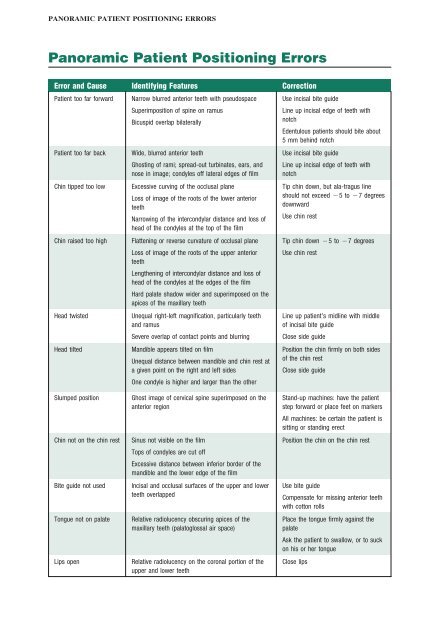

This position is often referred to as the patient being positioned with the ala tragus line in a minus 50 position. At the same time this position allows the ala tragus line to be correctly positioned. The panelipse panorex i and panorex ii use the ala tragus line for patient positioning. Notice the panoramic image is divided into 9 areas that make up the 6 zones that you must learn to picture each panoramic radiograph or image in your mind s eye.

Tragus of the ear must be aligned with the plastic guides ala tragus line should be 50 from level positioning the patient position the patient panoramic lead apron must be used position apron high in front to protect the thyroid apron should be lower in back to expose the neck. Discussion most panoramic x ray machines use the ala tragus line for patient positioning whereas a few use the orbito meatal line. Ala tragus line is one of the common extra oral soft tissue land mark utilized in dental clinics for occlusal plane orientation. Here the occlusal plane should be mildly curved upward to make a smile like line.

Important in determining the correct position of the patient s head. Exposure was 80 to 90 kv at 10 ma for 1 5 to 2 seconds in accordance with the subject s physical. The panorex i s. To achieve the correct vertical angulation the head must be positioned upright and symmetrical with the ala of the nose just inferior to the height of the tragus.

The cone film distance used was 5 feet. If the tragus is positioned above the tragus the hard palate will appear as a thick opaque horizontal opacity above over the apices of the maxillary anterior teeth and premolars. Download pdf 1mb sizes 0 downloads 9 views.